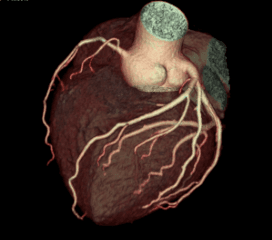

Cardiac CT imaging is a non-invasive diagnostic technique that uses advanced computed tomography technology to create detailed images of the heart and coronary arteries. Our revolutionary CT scanner can capture the entire heart in just one rotation, providing exceptional image quality with minimal radiation exposure.

This advanced imaging technique allows for comprehensive evaluation of cardiac structures, coronary arteries, and heart function, enabling early detection and accurate diagnosis of various heart conditions.

STRUCTURE ANALYSIS

- •Heart chambers assessment

- •Heart valve evaluation

- •3D cardiac reconstruction